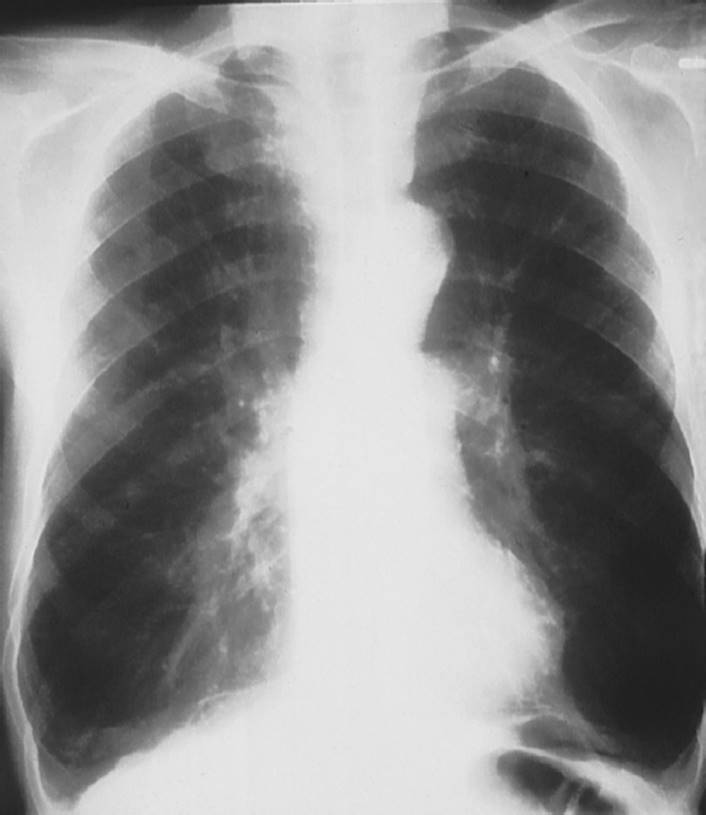

Emphysema is the second most prevalent disease within the category of COPD, with only asthma having a higher incidence. Emphysema is characterized by abnormal, irreversible enlargement of the airways distal to the terminal bronchioles, leading to decrease in driving pressure and intraluminal pressure, which leads to the impairment in expiratory airflow and maintenance of airway patency during inspiration28,29 (see Figs. 7-4 and 7-5). This may result in destruction of the acini, which are the functional units of the lungs for gas exchange. Each acinus is composed of one to three respiratory bronchioles and the alveolar ducts and sacs.

FIGURE 7-4 Emphysema. Notice the hyperinflation of the lungs on this P-A (posterior-anterior) X-ray with flattening of the diaphragm and elongation of the cardiac silhouette. (Courtesy of Dana Gryzbicki, MD, University of Pittsburgh, PA.)